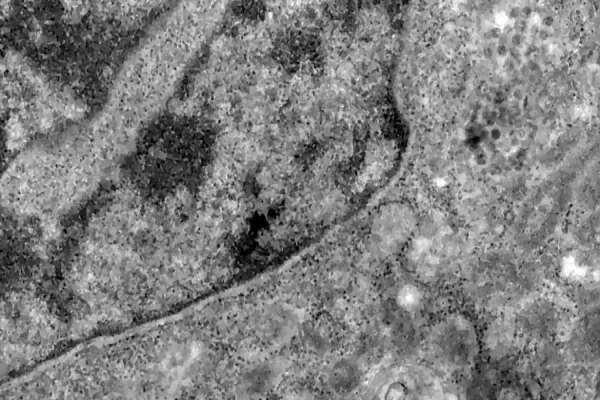

Nos casos analisados, constatou-se que a variante é portadora de dezenas de mutações genéticas que podem afetar os índices de contágio e de letalidade. A OMS, entretanto, afirmou que ainda não há estudos suficientes para afirmar as propriedades da Ômicron, mas que já existem esforços científicos acelerados para estudar as amostras. Um time de cientistas de universidades da África do Sul está decodificando o genoma da Ômicron, juntamente com dezenas de outras variantes do novo coronavírus.

Tulio de Oliveira, diretor do Centro para Respostas e Inovações Epidêmicas da universidade de KwaZulu-Natal, afirmou em coletiva de imprensa que a variante Ômicron possui “uma constelação incomum de mutações”. A variante Delta, por exemplo, possuía duas mutações em relação à cepa original do novo coronavírus, enquanto a Ômicron possui cerca de 50 - 30 delas localizadas na proteína Spike, responsável por infectar células saudáveis, explicou o brasileiro.